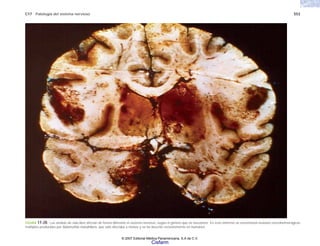

FIGURA 2-1. Glóbulos rojos de un caso de anemia de células falciformes. (Cortesía del Dr. Joaquín Carrillo).